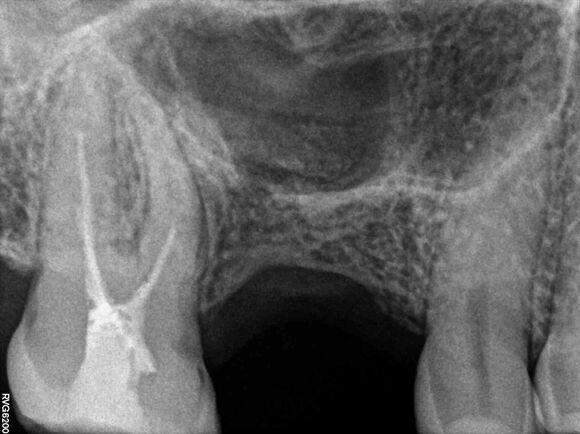

Beispiel 2: Vorher

Ausgedehnte Entzündung neben einem Implantat, bei diesem Überweisungsfall.

Beispiel 2: Nachher

Nur 6 Monate später ist die Entzündung fast vollständig zurückgegangen - Zahn und Implantat sind gerettet.